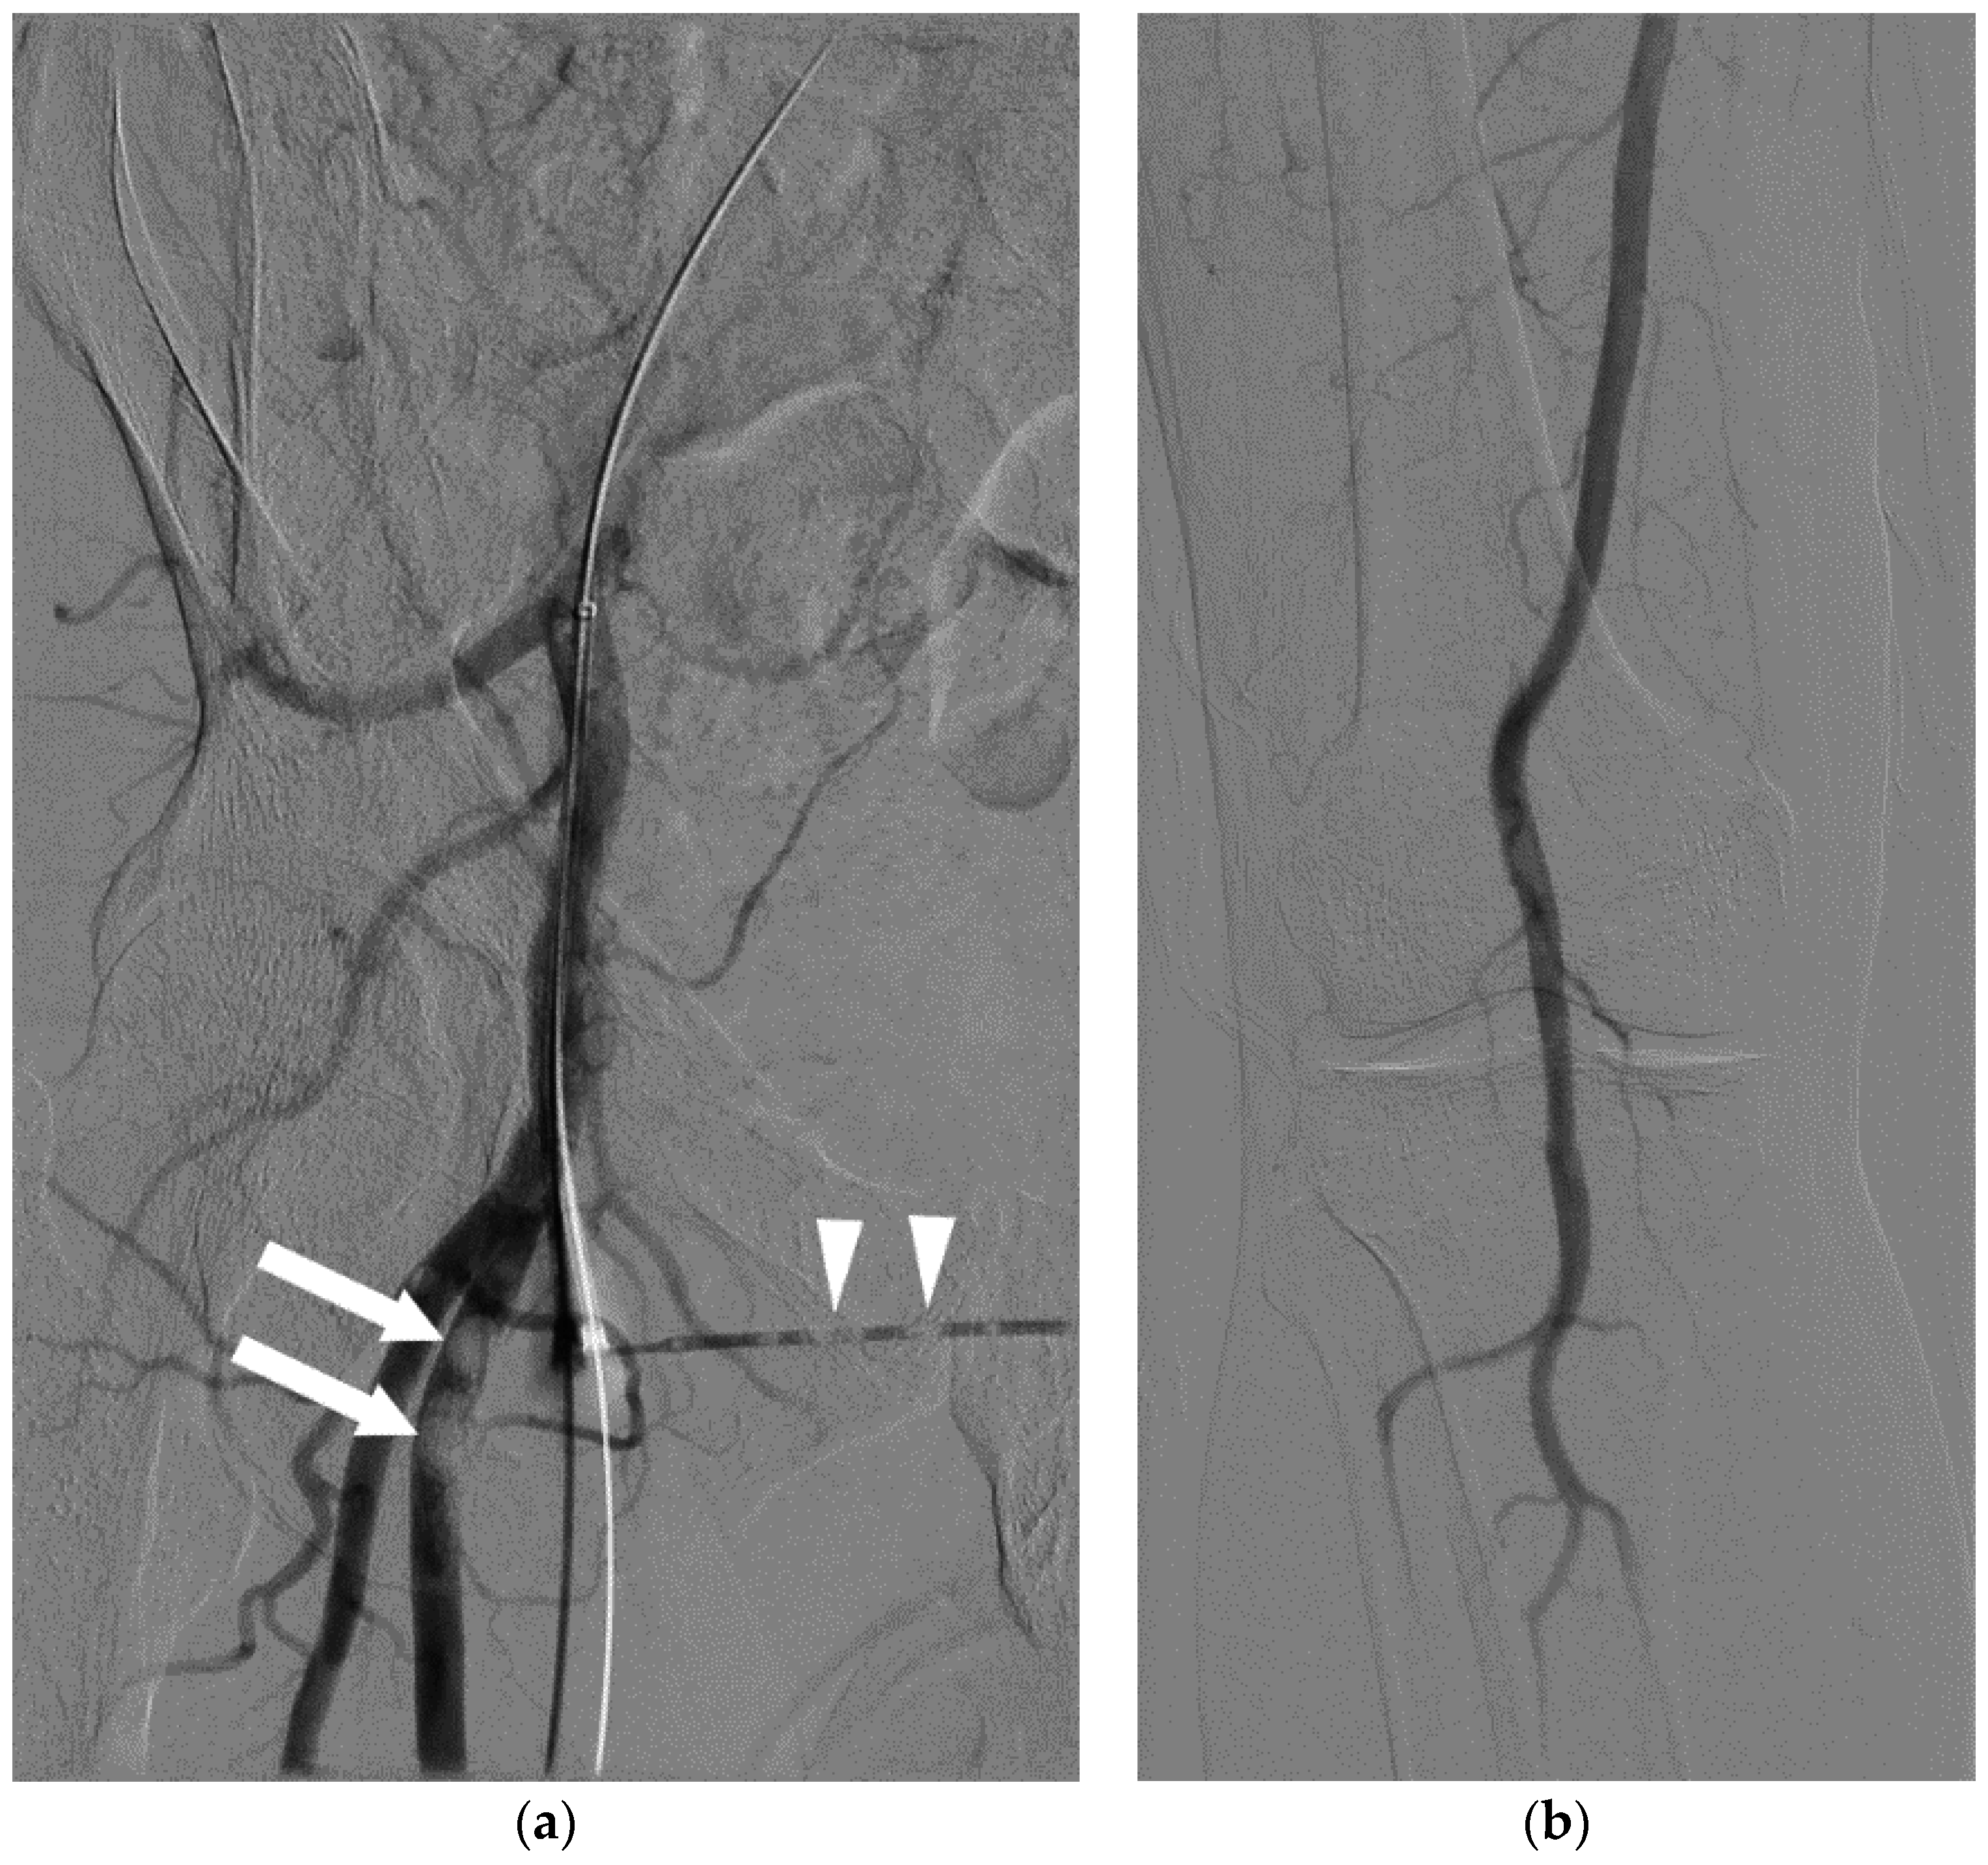

Figure 3.

A 69-year-old man who was critically ill with sepsis, pneumonia, and Cerebral Vascular Accident (CVA). Immediately after his pulmonary arterial line was pulled, he developed sudden cardiopulmonary arrest, suspected to be related to air embolism. A post-mortem CT (a–c) was performed 18 h later, revealing intravascular air in the ascending aorta (a, arrow), pulmonary artery (b, arrowhead), right ventricle (c, *) and the liver (arrow). Given the extent of air, it was considered most likely that the air was related to post-mortem state. Despite these findings, even when the heart was opened under water at autopsy, no air escaped, highlighting the difficulty in diagnosis of air embolism in some cases.